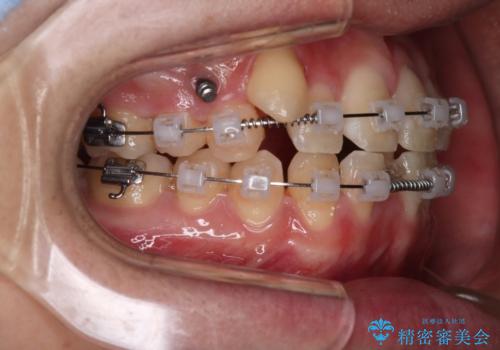

- クリア装置

歯の移動にオープンコイルとMI(歯肉に埋入するネジ)を用いました。

非抜歯矯正だったこともあり、1年半以内という短い期間で矯正を終了することができました。